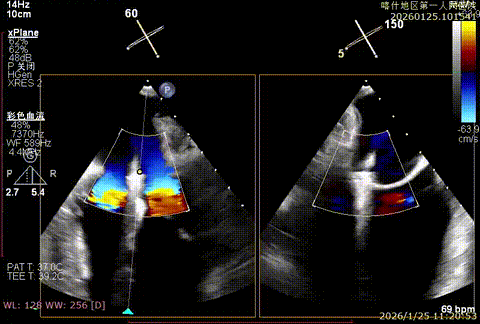

重度反流

反流降低

该例患者为DMR,脱垂区域较宽,术前制定手术策略:使用2把XTR先于患者外侧交界至1区部位进行钳夹。术中房间隔穿刺高度为4.0cm。成功穿刺后将SGC和XTR-CDS依次送入左心房,通过操控“M”旋钮调节SGC,使二尖瓣夹避开华法林脊,成功定位于2区正上方。在2区进行弹道测试成功后,进行Orientation调整。第一把于外侧交界区夹持,第二把于1区夹持,术中成功捕捞和夹持瓣叶后缓慢关紧夹臂,TEE检查见二尖瓣反流程度降低至1+,术后平均跨瓣压差3mmHg,手术顺利结束。

术后平均跨瓣压差3mmHg